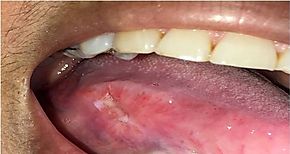

El cáncer bucal es una úlcera que no cicatriza, da molestias ligeras y se manifiesta...